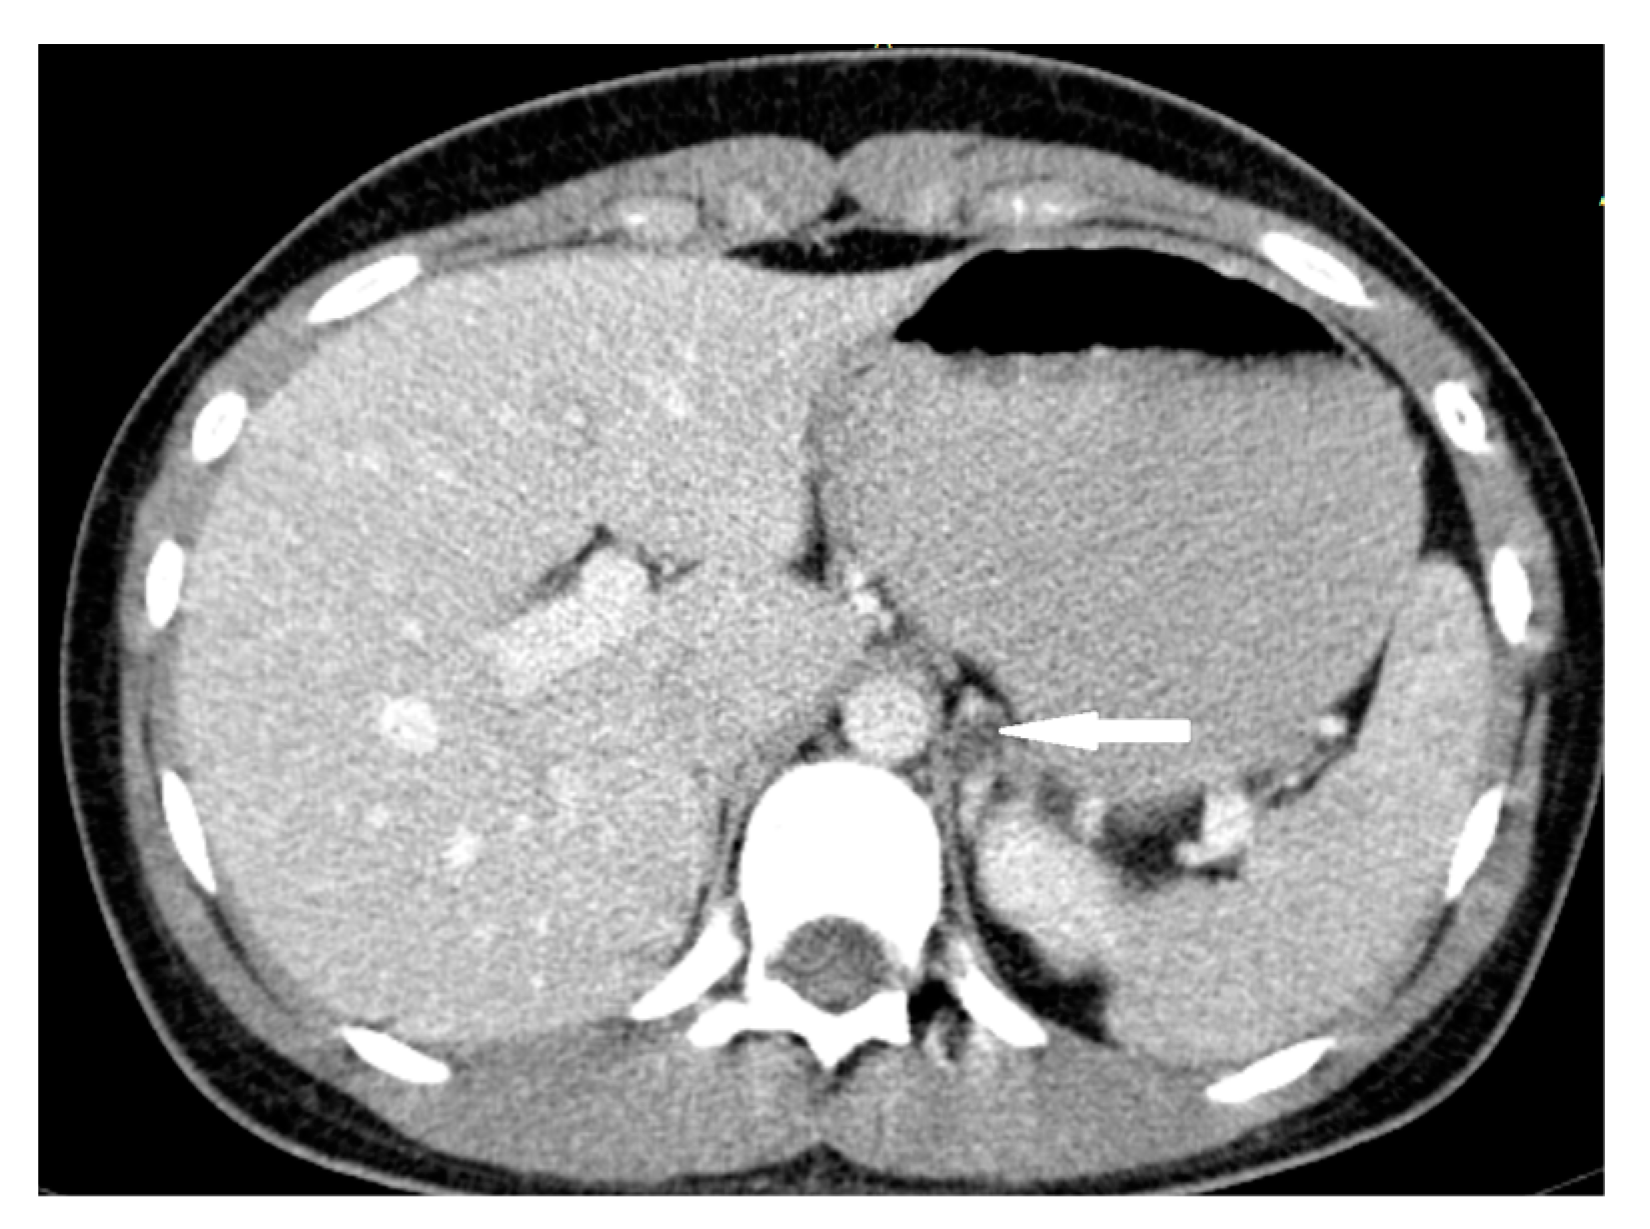

2.3. Case 3